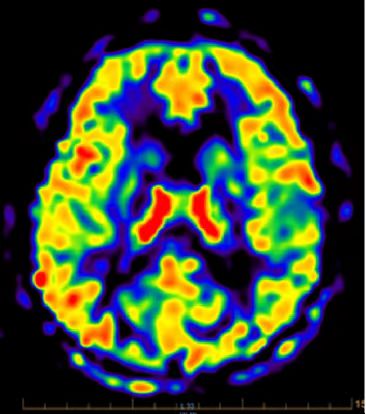

中枢神经系统方向

扩散张量成像(DTI),观察脑白质纤维束的走形、完整性及方向性,可用于描述脑肿瘤与邻近纤维束的关系、观察脑发育等。动脉自旋标记技术(ASL),是一种不打药的血管成像技术,主要作用是用来做磁共振灌注成像。省去了打药的过程,不打药灌注的检查就非常的安全,并且操作方便,便于随访或者复查。采用4D ASL技术,可以不打药(不增强),得到动态的类DSA效果的血管流入流出图像(即4D MRA效果),对于显示血管疾病,特别是Moyamoya、AVM(动静脉畸形)、AVF(动静脉瘘)、血管旁路手术评估、颅内肿瘤血供来源分析等非常有用。磁敏感加权成像(SWI)是一种利用组织间磁敏感性差异及血 氧水平依赖(BOLD)效应成像的磁共振新技术。SWI显示静脉结构、血液代谢产物、矿物质沉积十分敏感,SWI对微出血病灶敏感度更高,在脑肿瘤、脑血管病、脑外伤及神经变性病等中枢神经系统病变中有较高的临床应用价值和广阔的临床应用前景。

磁共振波谱成像(MRS)是目前唯一能无创观察活体组织代谢及生化变化的技术,对脑肿瘤的诊断和鉴别诊断有很大的价值。